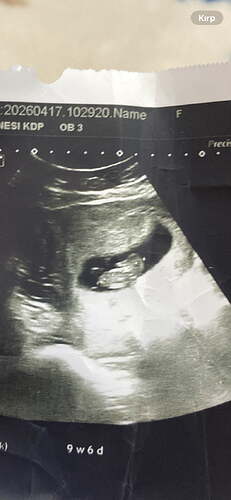

Neye bakarak erkek hissi verdi . Bende ayırt etmek istiyorum çünkü bakınca bana hem kız hissi veriyor hem erkek ![]()

His bilemiyorum. Kafası daha büyük oluyo bide

Erkek bence

Bence kız mercimek gibi olursa kız derler fasulye gibi olurs erkek derler hakkında hayırlısı olsun canım